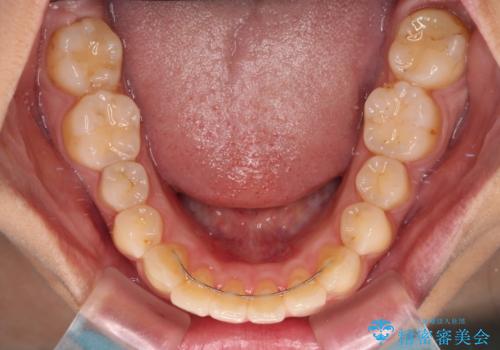

前に出ている前歯を引っ込めたい インビザライン矯正

- 前方に傾斜した上下の前歯を気にして来院された患者様です。

唇の閉じにくさや横顔のシルエットが気になるような突出感ではなかったため、インビザラインを用いて、歯列の遠心移動とIPR(歯と歯の間を削る)により前歯の傾斜を改善していくこととしました。

スムーズに終了すると思われましたが、インビザライン矯正独特の奥歯が咬み合わない状態が続き、更には遠方へ転居されたこともあり、治療期間は長引いてしまいました。